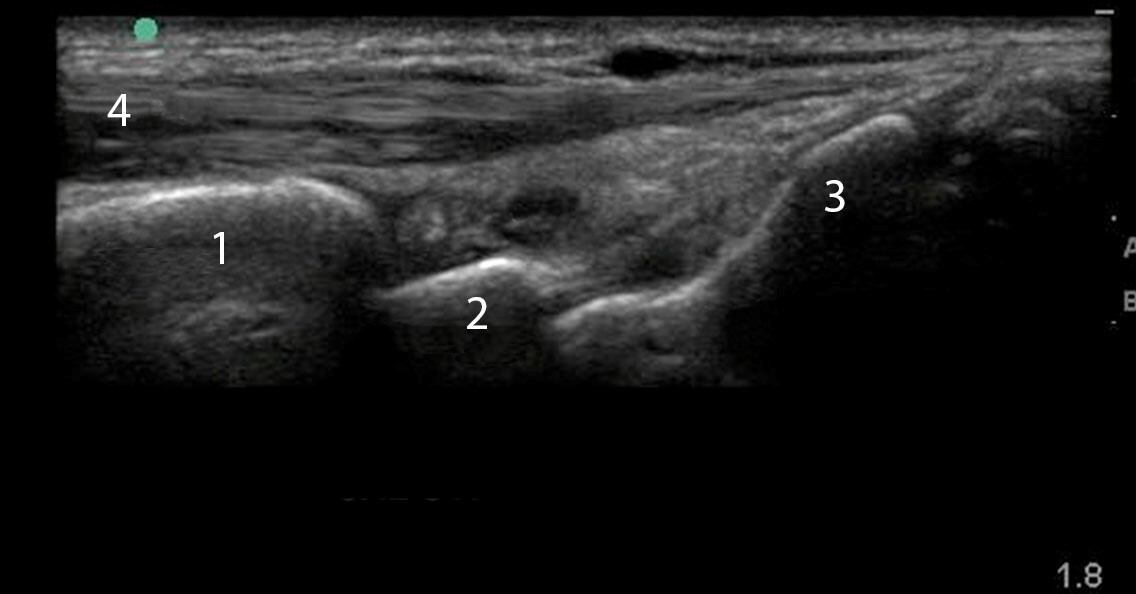

Dorsal Wrist Synovitis Longitudinal Image

Radius

Lunate

Capitate

Extensor Tendon